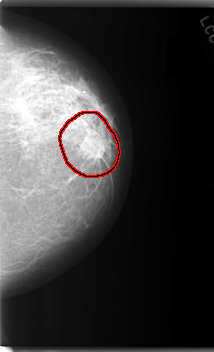

C_0116_1.LEFT_MLO

LEFT_MLO LINES 5896 PIXELS_PER_LINE 3920 BITS_PER_PIXEL 12 RESOLUTION 50 OVERLAY

FILE: C_0116_1.LEFT_MLO.OVERLAY

TOTAL_ABNORMALITIES 1

ABNORMALITY 1

LESION_TYPE MASS SHAPE IRREGULAR MARGINS SPICULATED

ASSESSMENT 5

SUBTLETY 5

PATHOLOGY MALIGNANT

TOTAL_OUTLINES 1

BOUNDARY